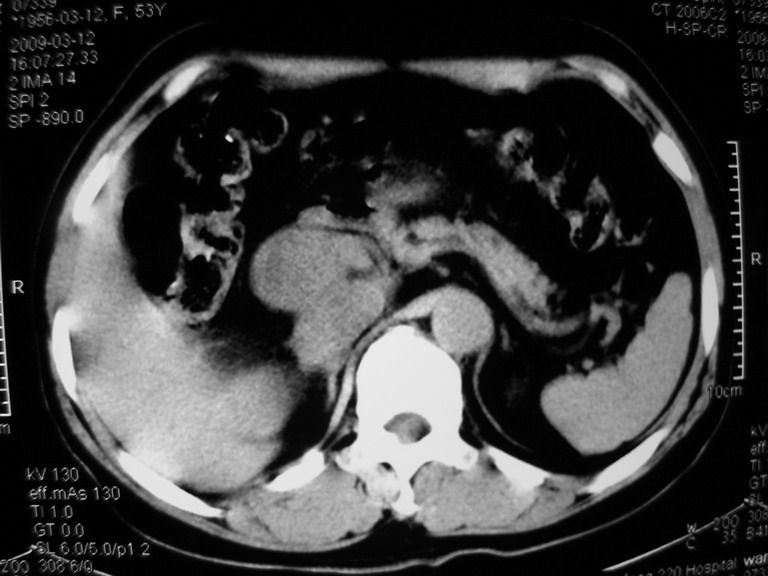

患者,女性50岁,上腹部不适2年余,既往多次腹部彩超未见异常,今日上午在我院查彩超发现肝右叶囊实性病变,外院辅助检查,afp,cea,ca199, 都在正常范围内,无肝炎史否认肿瘤史,生活在牧区

接着往下一贴看,有静脉期和延迟期,在看看和下腔静脉及十二指肠的关系,腔静脉内是不是栓子?

考虑肝右叶与尾叶交界区肝癌(部分外生),侵犯下腔静脉并下腔静脉瘤栓形成。

肝包虫病可能性大